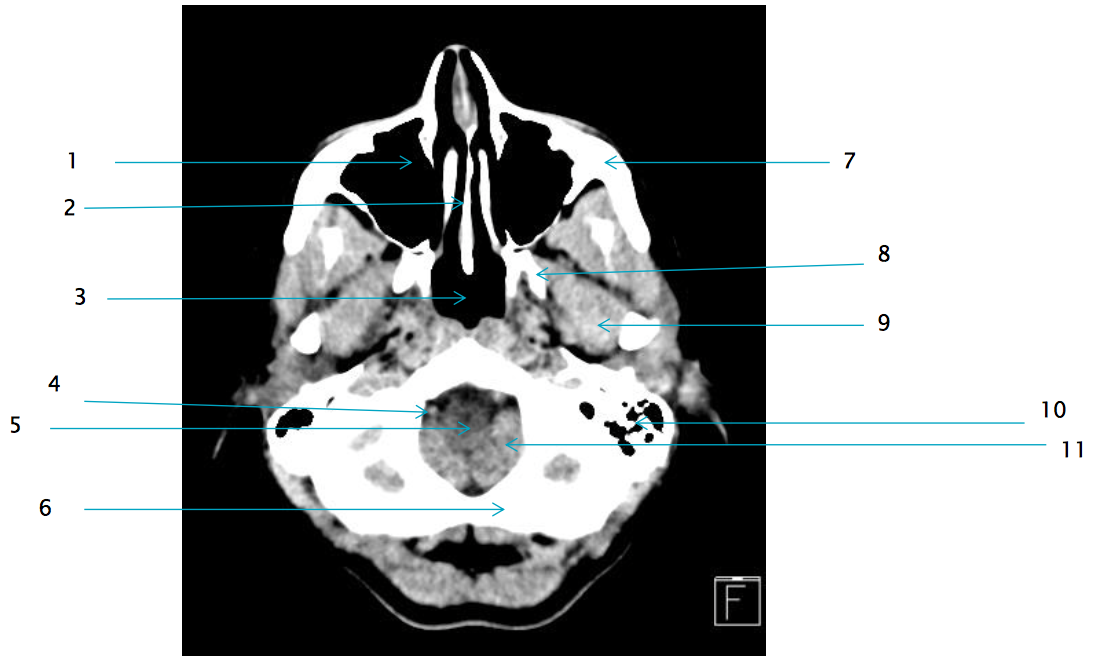

6

L occipital bone

7

L zygomatic arch

8

L lateral pterygoid plate

11

L Cerebellar tonsil

9

L lateral pterygoid muscle

1

R maxillary sinus

2

vomer

5

medulla oblongata

10

L mastoid air cells